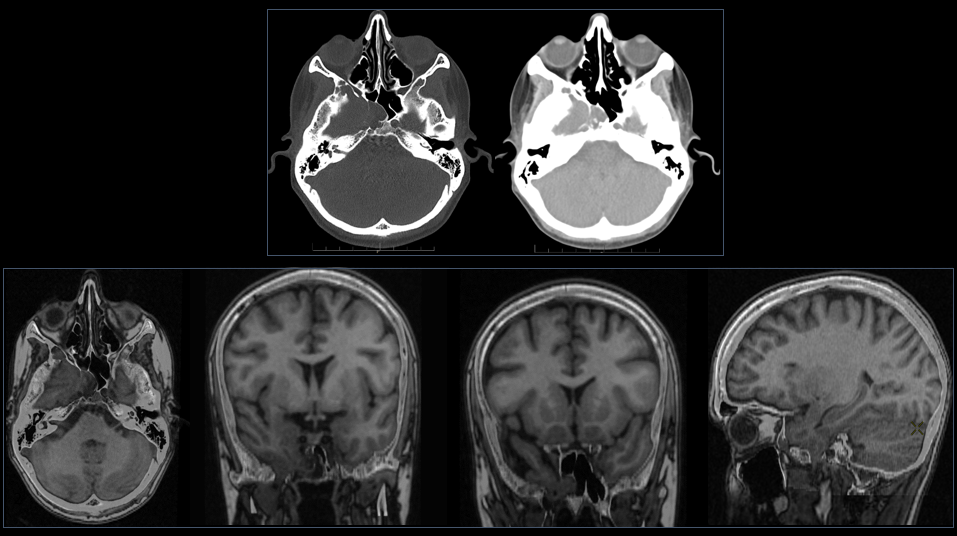

A su llegada a urgencias se realiza TC craneal y posteriormente se amplia estudio con RM.

(1) TC basal axial con ventana de hueso y con ventana de partes blandas: remodelado óseo del hemiclivus derecho, del foramen oval derecho y del ala esfenoidal mayor con contenido de partes blandas. Se decide ampliar estudio mediante RM de forma programada.

(2) Fusión TC + RM en secuencia T1 en planos axial, coronal y sagital: lesión expansiva insuflante en base de cráneo que ocasiona remodelado óseo y de contenido sólido-quístico Además se aprecia una continuidad del polo temporal con el componente sólido. Las características descritas en el contexto clínico sugieren encefalocele.